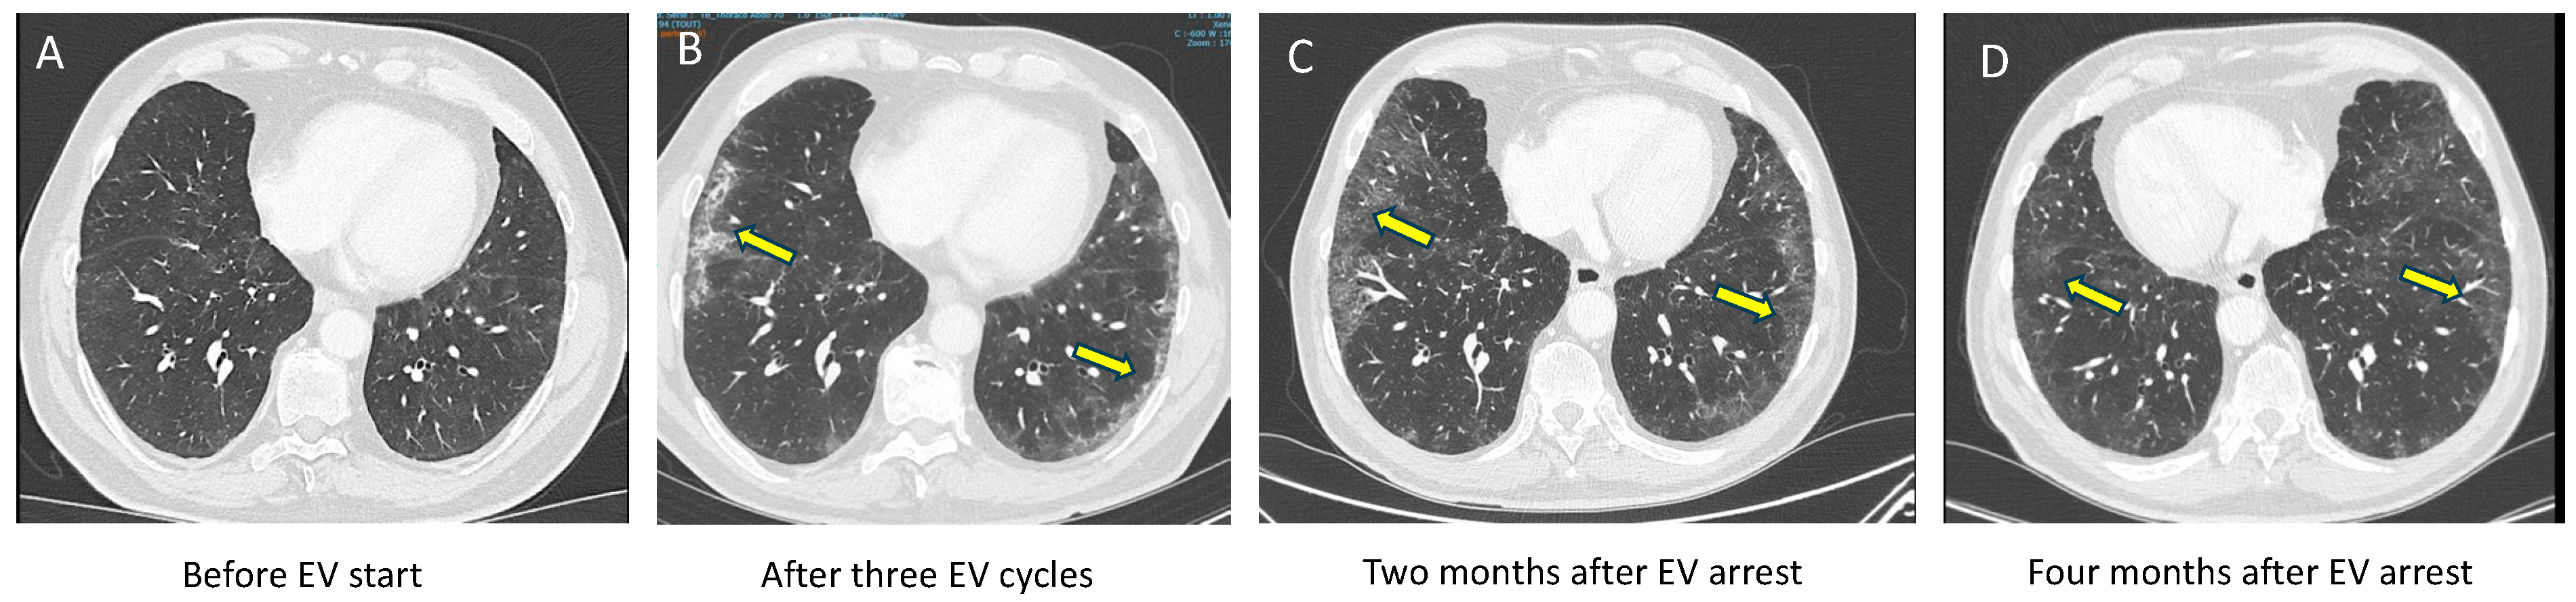

2.1. Case 1 (Priming Patient)